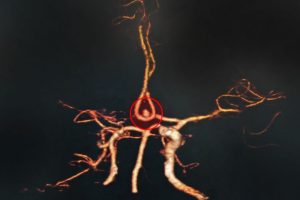

Bệnh viện Đa khoa Xuyên Á – Vĩnh Long (BVXA – VL) đã tiến hành phẫu thuật tạo hình thân sống bằng phương pháp bơm cement sinh học điều trị thành công cho hai bệnh nhân lớn tuổi bị xẹp đốt sống do loãng xương.